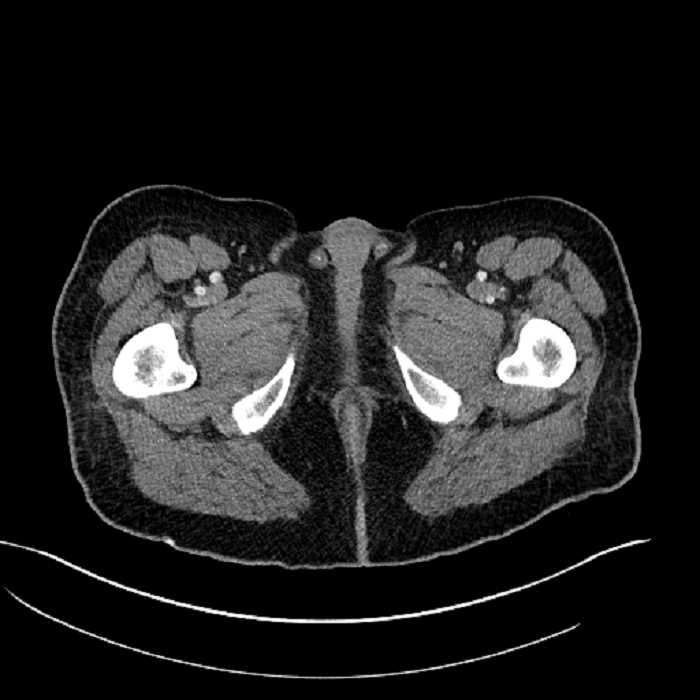

Age: 63

Sex: Male

Indication: Abdominal pain

• High grade stenosis of the left common iliac artery, with the left internal and external iliac arteries remaining patent

• Ankylosis of both sacroiliac joints

Acute sigmoid diverticulitis complicated by a small contained perforation and a large abscess in the right hepatic lobe. Additional small subcapsular abscesses along the anterior margin of the left hepatic lobe.

Additionally, loss of the normal fat plane between the peridiverticular collection and adjacent thickened loops of small bowel raises the potential for an enterocolonic fistula.

High grade stenosis of the left common iliac artery. The left external and internal iliac arteries are patent.

Hepatic abscess showing the double target sign with low density internally surrounded by a thin inner enhancing rim (red arrow) and ill-defined outer low density rim (yellow arrow). Blue arrow indicates an internal septation. Red arrows: additional smaller subcapsular abscesses. Red arrow: focal contained perforation associated with diverticulitis.